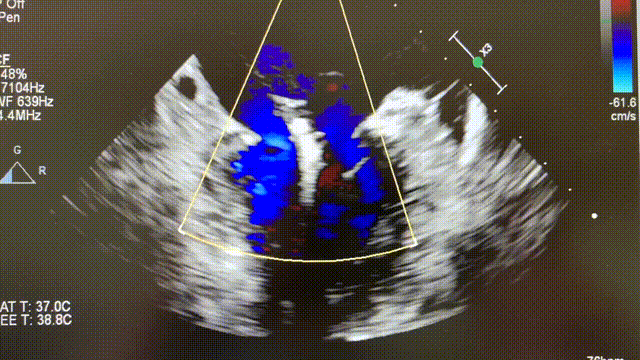

术前彩超

术中操作时,患者全麻,经右侧股静脉穿刺,通过MitraClip®独特的三层双调弯设计输送系统,顺利将导管送入左心房和左心室,到达二尖瓣膜目标位置。随后,在经食道超声及数字减影血管造影技术引导下,陈茂教授释放MitraClip®夹合器,准确捕获并固定二尖瓣瓣叶,“缘对缘”技术使二尖瓣在由大的单孔变成小的双孔,从而达到减少二尖瓣反流的效果。

术后影像

夹合器释放后,超声显示反流明显减少,患者各项生理指标正常,手术顺利完成,整场手术耗时约120分钟。